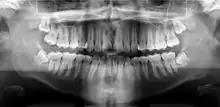

A panoramic radiograph of a 9 year old in mixed dentition

A basic panoramic radiograph